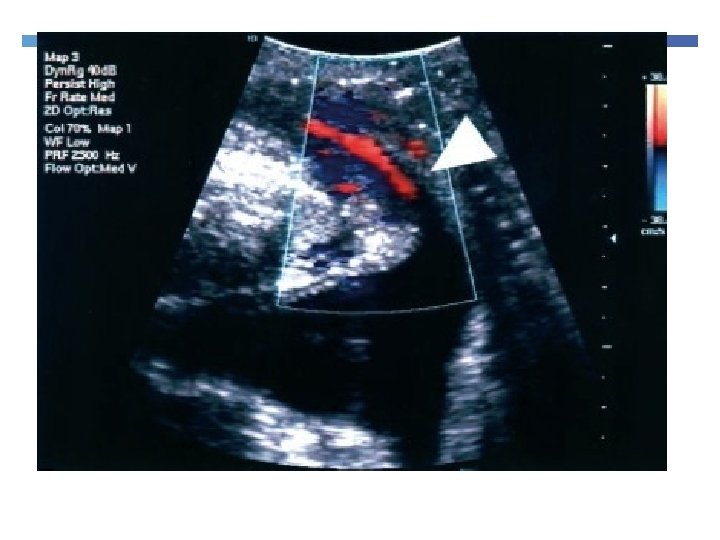

6. Exclude other pathology

7. Evaluate sling complication

Imaging Slings Useful in voiding dysfunction post tape insertion Failed tapes Helps to see if tape has indeed been cut

8. Evaluate voiding dysfunction